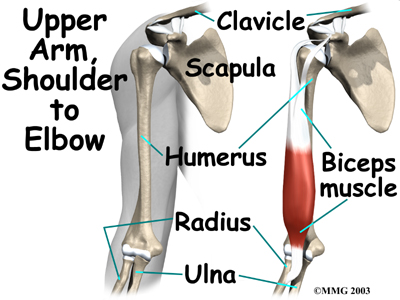

The biceps muscle goes from the shoulder to the elbow on the front of the upper arm. Tendons attach muscles to bone. Two separate tendons connect the upper part of the biceps muscle to the shoulder. One tendon connects the lower end of the biceps to the elbow.

The lower biceps tendon is called the distal biceps tendon. The word distal means that the tendon is further down the arm. The upper two tendons of the biceps are called the proximal biceps tendons, because they are closer to the top of the arm.

The attaches to a small bump on the radius bone of the forearm. This small bony bump is called the radial tuberosity. The radius is the smaller of the two bones between the elbow and the wrist that make up the forearm. The radius goes from the outside edge of the elbow to the thumb side of the wrist. It parallels the larger bone of the forearm, the ulna. The ulna goes from the inside edge of the elbow to the wrist.

The upper (proximal) end of the biceps has to the shoulder. The main attachment is the long head of the biceps. It connects the biceps muscle to the top of the shoulder socket, called the glenoid. The short head of the biceps angles up and in to its attachment on the corocoid process of the shoulder blade. The corocoid process is a small bony knob in the front of the shoulder.